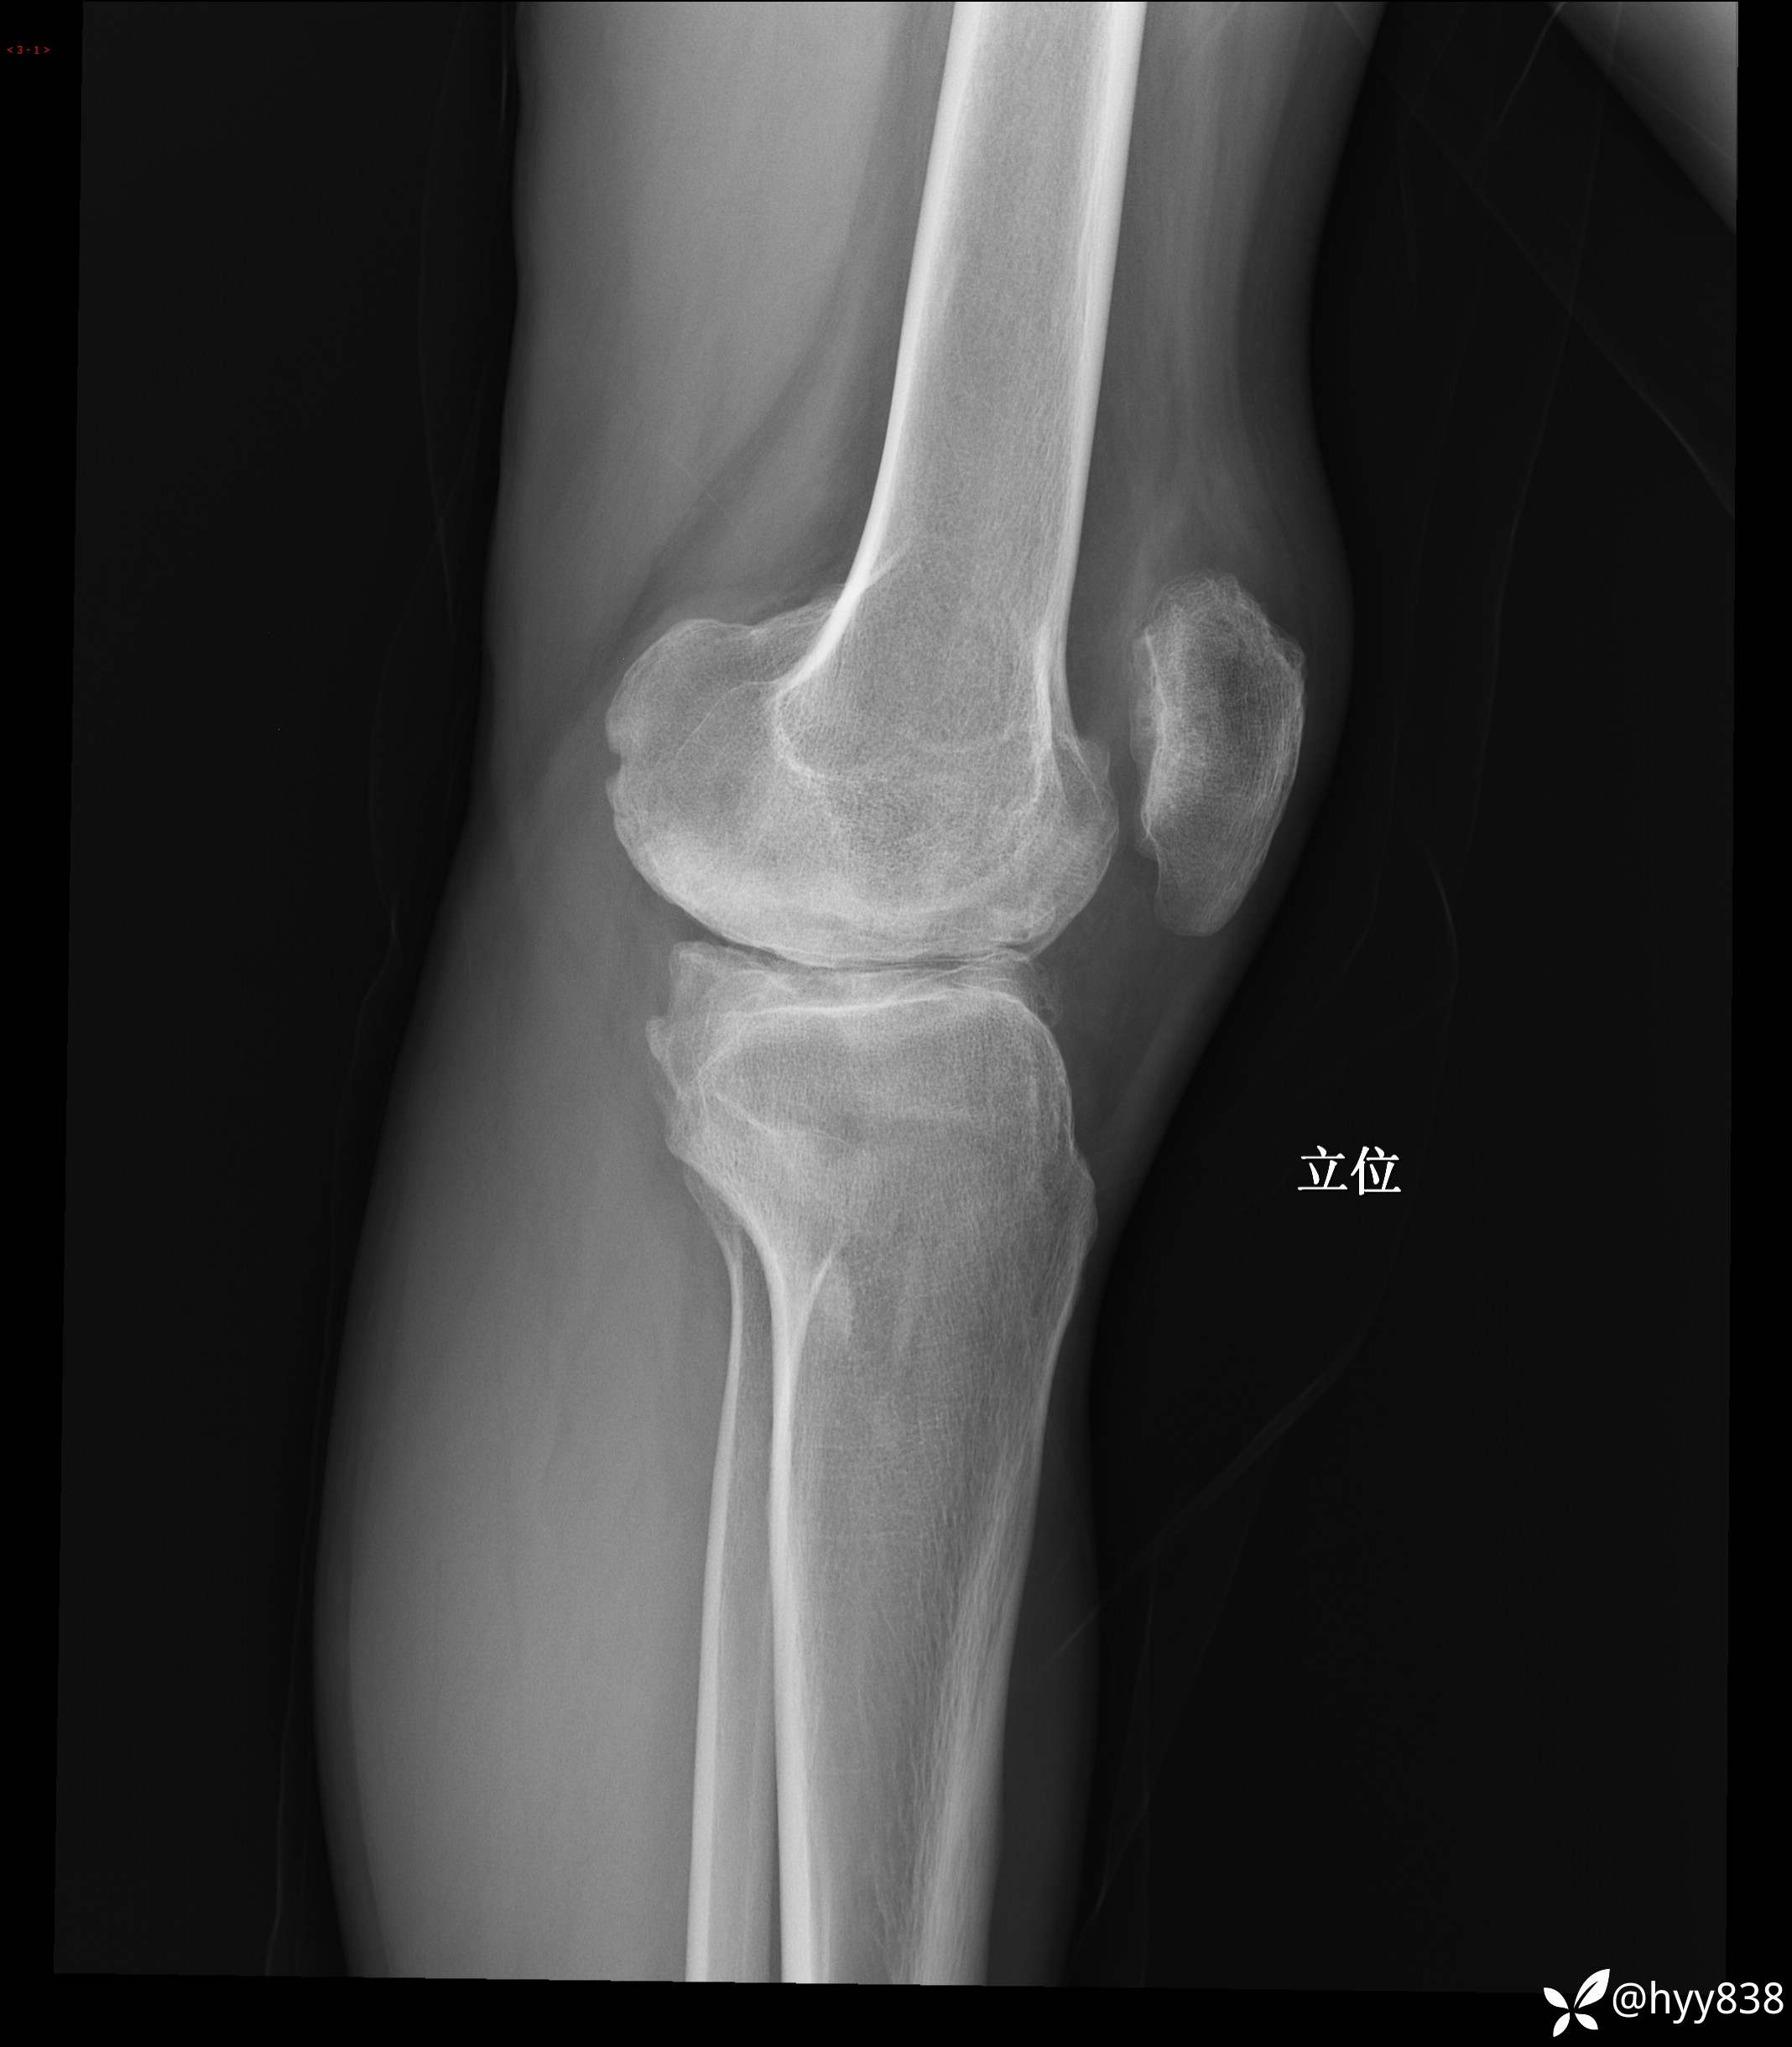

膝关节平片